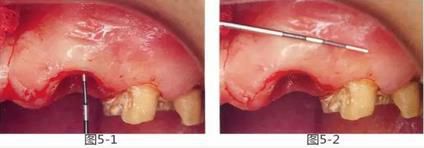

圖5-1,2

存在齦下齲壞。術(shù)前的穿刺檢查表明,從齦緣到牙槽嵴頂?shù)木嚯x在2mm以內(nèi)。角化齦寬度為5mm左右。